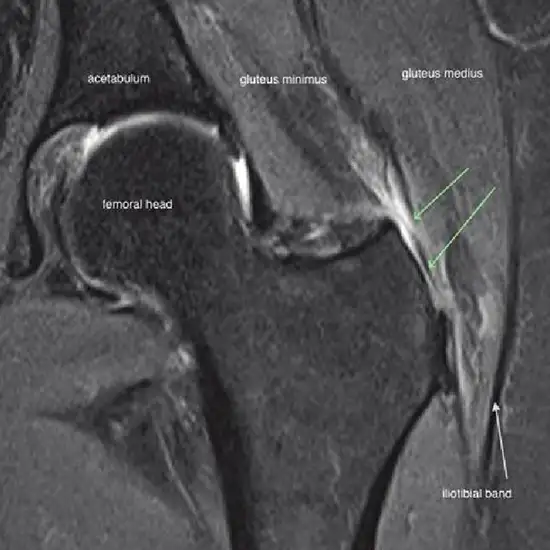

MRI (Magnetic resonance imaging) Gluteal and Spine is an imaging procedure to look at the gluteal region, spine column, and surrounding tissues. This procedure obtains high-resolution pictures to diagnose and detect the problems associated with muscles in the gluteal region, spinal cord, muscles, disc, and soft tissues.